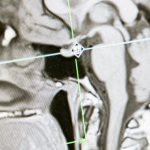

La thérapie au laser, également connue sous le nom de photobiomodulation, utilise des longueurs d’onde spécifiques pour cibler les tissus affligés. Lorsqu’un laser à faible intensité pénètre dans les tissus, il est absorbé par les mitochondries des cellules. Ce processus déclenche la production d’ATP (adénosine triphosphate), la molécule qui fournit l’énergie nécessaire aux cellules pour la guérison et la réparation. En augmentant la production d’ATP, le laser favorise donc la régénération cellulaire, permettant ainsi aux tissus de se rétablir plus rapidement.

La thérapie au laser fonctionne grâce au processus de photobiomodulation, où la lumière est absorbée par les mitochondries des cellules cibles, augmentant ainsi la production d’ATP (adénosine triphosphate). Ce processus génère l’énergie nécessaire à la réparation tissulaire, réduisant ainsi l’inflammation et favorisant la circulation sanguine dans les zones touchées. En boostant la régénération cellulaire, la thérapie au laser aide à diminuer la douleur et à améliorer la mobilité des tissus affectés.